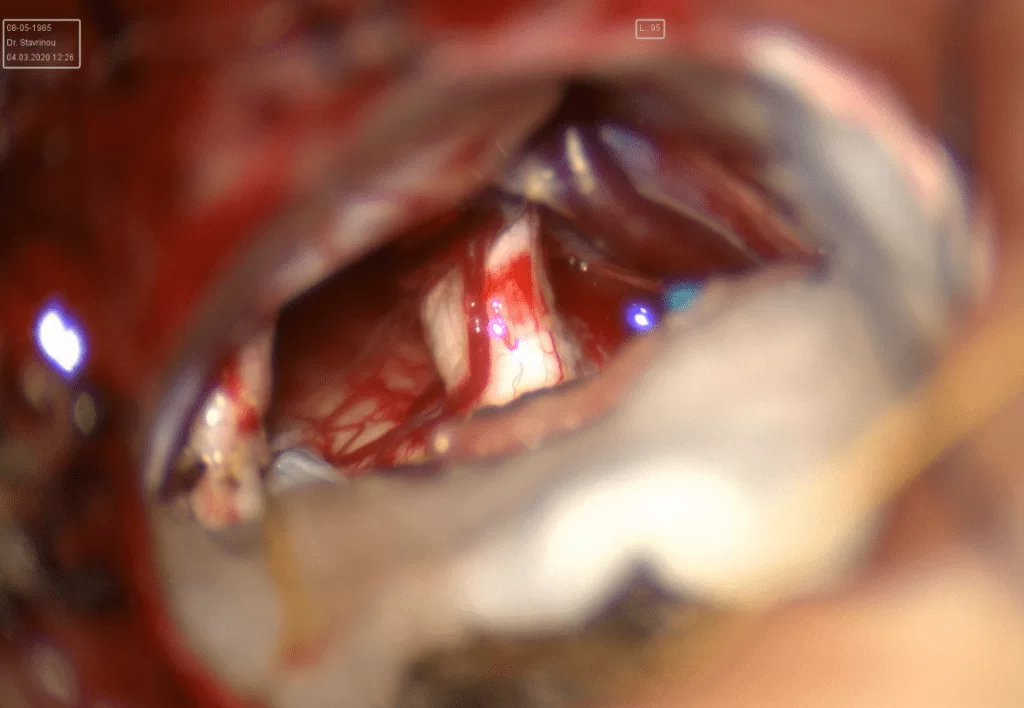

Τεχνικές: Η υπερκόγχιος κρανιοτομία (προσπέλαση μέσα από το φρύδι):

Η υπερκόγχιος κρανιοτομία με τομή μέσα στο φρύδι του ασθενούς είναι χρήσιμη σε ασθενείς με μηνιγγιώματα, κρανιοφαρυγγιώματα αλλά και άλλους όγκους κοντά στα οπτικά νεύρα και την υπόφυση.

Αυτή η ευέλικτη, ελάχιστα επεμβατική προσέγγιση ελαχιστοποιεί τη βλάβη στους πέριξ ιστούς και την έλξη του εγκεφάλου που συχνά απαιτείται με πιο συμβατικές προσπελάσεις, επιτρέποντας μια πιο άμεση προσέγγιση αυτών των όγκων. Συχνά συνδυάζεται με τη χρήση του ενδοσκοπίου (ενδοσκοπικώς υποβοηθούμενη κρανιοτομία) το οποίο αυξάνει τον έλεγχο των κρίσιμων δομών.

Ένα επίσης σημαντικό πλεονέκτημα της μεθόδου είναι το άριστο αισθητικό αποτέλεσμα (Εικόνα 1 & 2).